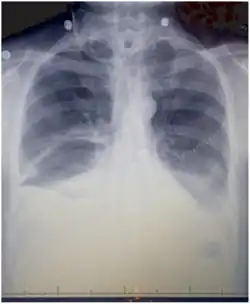

Chest X-rays can detect a chylothorax. It appears as a dense, homogeneous area that obscures the costophrenic and cardiophrenic angles. Ultrasounds can also detect a chylothorax, which appears as an echoic region that is isodense with no septation or loculation. However, neither a normal chest x-ray nor an ultrasound can differentiate a chylothorax from any other type of pleural effusion.[1]

The cisterna chyli can be found in a thoracic MRI, making it possible to confirm chylothorax. However, MRI is not the ideal method to scan the thorax, and so it is rarely used. Another diagnostic technique is conventional lymphangiography. It is rarely used since there are equally sensitive yet less invasive techniques available to identify a chylothorax. Lymphangiography procedures use the contrast dye agent lipiodol, which is injected into the lymphatic vessels. The chylothorax shows up on the images and identifies the source any leak in the thoracic duct.[1]